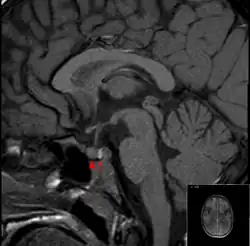

Típica glândula pituitária vista por ressonância magnética (sagital T1 sem meio de contraste). A seta indica a glândula pituitária posterior (sinais fortes) e a ponta da seta a glândula pituitária anterior

O exame comprobatório gold standard para diagnóstico da apoplexia pituitária é a ressonância magnética, que tem uma sensibilidade superior a 90% para detectar a doença, podendo identificar isquemia (dano tecidual devido à redução do suprimento sanguíneo) ou hemorragia.[1] Podem ser utilizadas várias sequências de ressonância magnética para determinar a ocorrência e a proporção da lesão (hemorragia ou isquemia).[7] Se a ressonância magnética não for indicada (por exemplo, se o paciente se encontra gravemente claustrofóbico ou se tiver implantes que contenham metal), a tomografia computadorizada pode demonstrar anomalias na glândula pituitária, não obstante a falta de fiabilidade.[1]Grande parte dos tumores hipofisários (25%) são detectados graças à individualização, na ressonância, das zonas do enfarte hemorrágico, porém a apoplexia não pode ser diagnosticada se não estiver acompanhada de sintomas.[1][4]